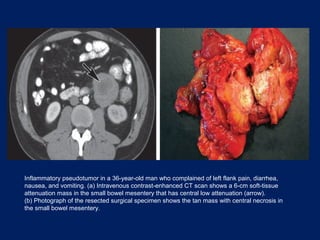

Inflammatory pseudotumor in a 36-year-old man who complained of left flank pain, diarrhea,

nausea, and vomiting. (a) Intravenous contrast-enhanced CT scan shows a 6-cm soft-tissue

attenuation mass in the small bowel mesentery that has central low attenuation (arrow).

(b) Photograph of the resected surgical specimen shows the tan mass with central necrosis in

the small bowel mesentery.